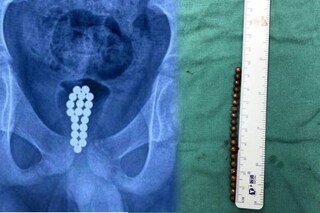

ഡോങ്ഗുവാനിലെ കുട്ടികളുടെ ആശുപത്രിയിലെ ചീഫ് യൂറോളജിസ്റ്റായ ഡോ. ലി ഹോങ്ഹുയി ആണ് എൻഡോസ്കോപ്പി നടത്തിയത്. ശസ്ത്രക്രിയ കൂടാതെ 20 കാന്തിക ഗോളങ്ങൾ പുറത്തെടുക്കുക അസാധ്യമായിരുന്നുവെന്നും അദ്ദേഹം പറഞ്ഞു. മൂത്രനാളിയിലൂടെ ഇവ പുറത്തെടുക്കുന്നത് പരിക്ക് ഗുരുതരമാകുമെന്ന ആശങ്കയും ഡോക്ടർ പങ്കുവെച്ചു. പിന്നീട് ശസ്ത്രക്രിയയിലൂടെ ബോളുകളെല്ലാം നീക്കം ചെയ്തു.